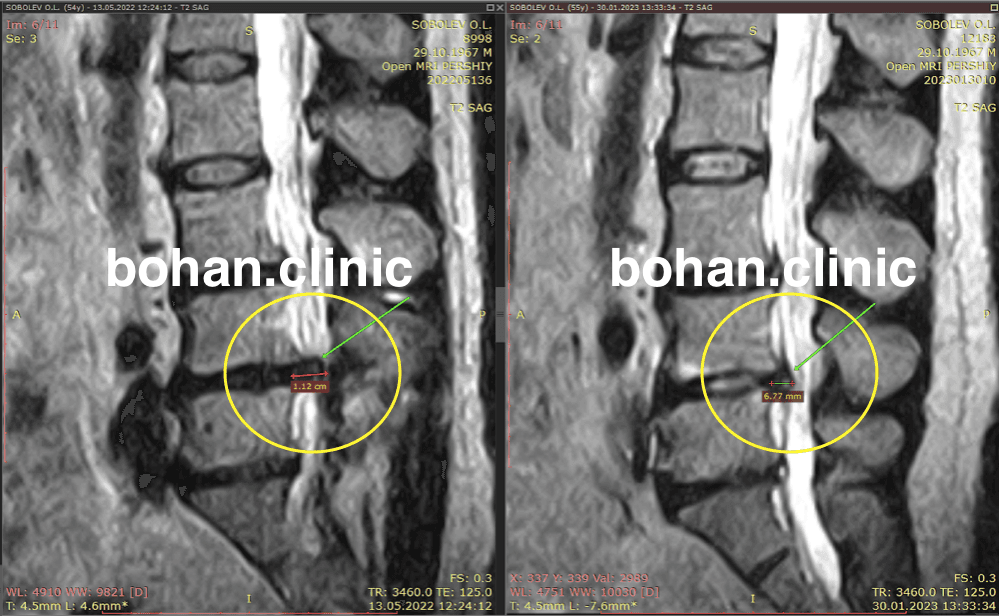

Метод лікування грижі шляхом стимуляції резорбції в Україні був впроваджений у 2020-2021 роках.  Алгоритм оцінки грижі на предмет резорбції, що використовується у клініках – є авторським, розроблений лікарем Боханом А.Ю.